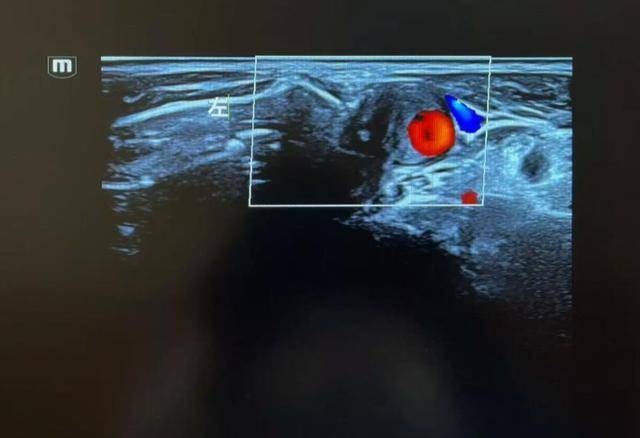

直到有一天,他在早市突然眼前一黑,差点摔倒。家人连忙送去医院,一查彩超,医生皱起了眉:“你的颈动脉堵了差不多70%,再拖下去,很容易发展成脑中风。”

判断颈动脉堵塞严重不严重,医生一般会两头一起看:影像学检查结果:例如颈动脉彩超、CTA,直接看到血管腔狭窄的比例;症状:有没有上述反复头晕、记忆力变差、小中风等表现。